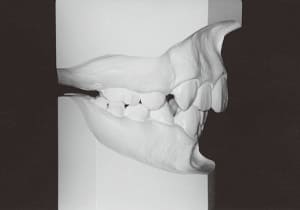

The Class II condition is pronounced, with a significant overjet of 12.5 mm(3). Although the teeth size are large, crowding is relatively mild. The maxillofacial structure has good depth and a robust bone framework(5). The mandible itself is solid , robust gonial angle, but there is significant anterior-posterior displacement relative to the maxilla(ANB 10.0°). While there is no confirmed history of thumb-sucking or similar habits, the lower lip is already pushing up against the maxillary incisors. The cause of this condition is unknown.

13 uperimposition on S–N and S

The first phase of treatment involved extracting the left and right maxillary deciduous canines. The space created was used to forcibly retract the four anterior teeth, thereby aiming to improve lip closure function (6–9, 11). Morphological changes suggest that lip function differed before and after treatment (6, 9). Subsequently, the first premolars erupted, but extraction is planned to secure space for canine eruption (10). A Class II molar relationship remains, but the significant overjet has improved (11).

The facial type changed from backward divergent to straight between the initial visit and after retention (27–31). Cephalometric X-rays reveal significant mandibular growth (32).